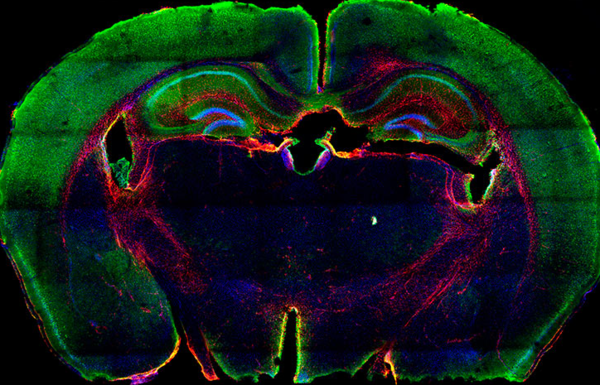

Imagen de CAS9 (verde) y GFAP (rojo) en una sección coronal del cerebro de un ratón TVA/Cas9. Crédito image: CNIO

Para lograr esto avance los investigadores, dirigidos por Massimo Squatrito, combinaron dos tecnologías utilizadas en la investigacion y control del cancer , la herramienta de edición genética CRISPR y el sistema de administración de genes RCAS/TVA , para generar un modelo de ratón que ofrece la posibilidad de imitar la complejidad genética del cáncer.